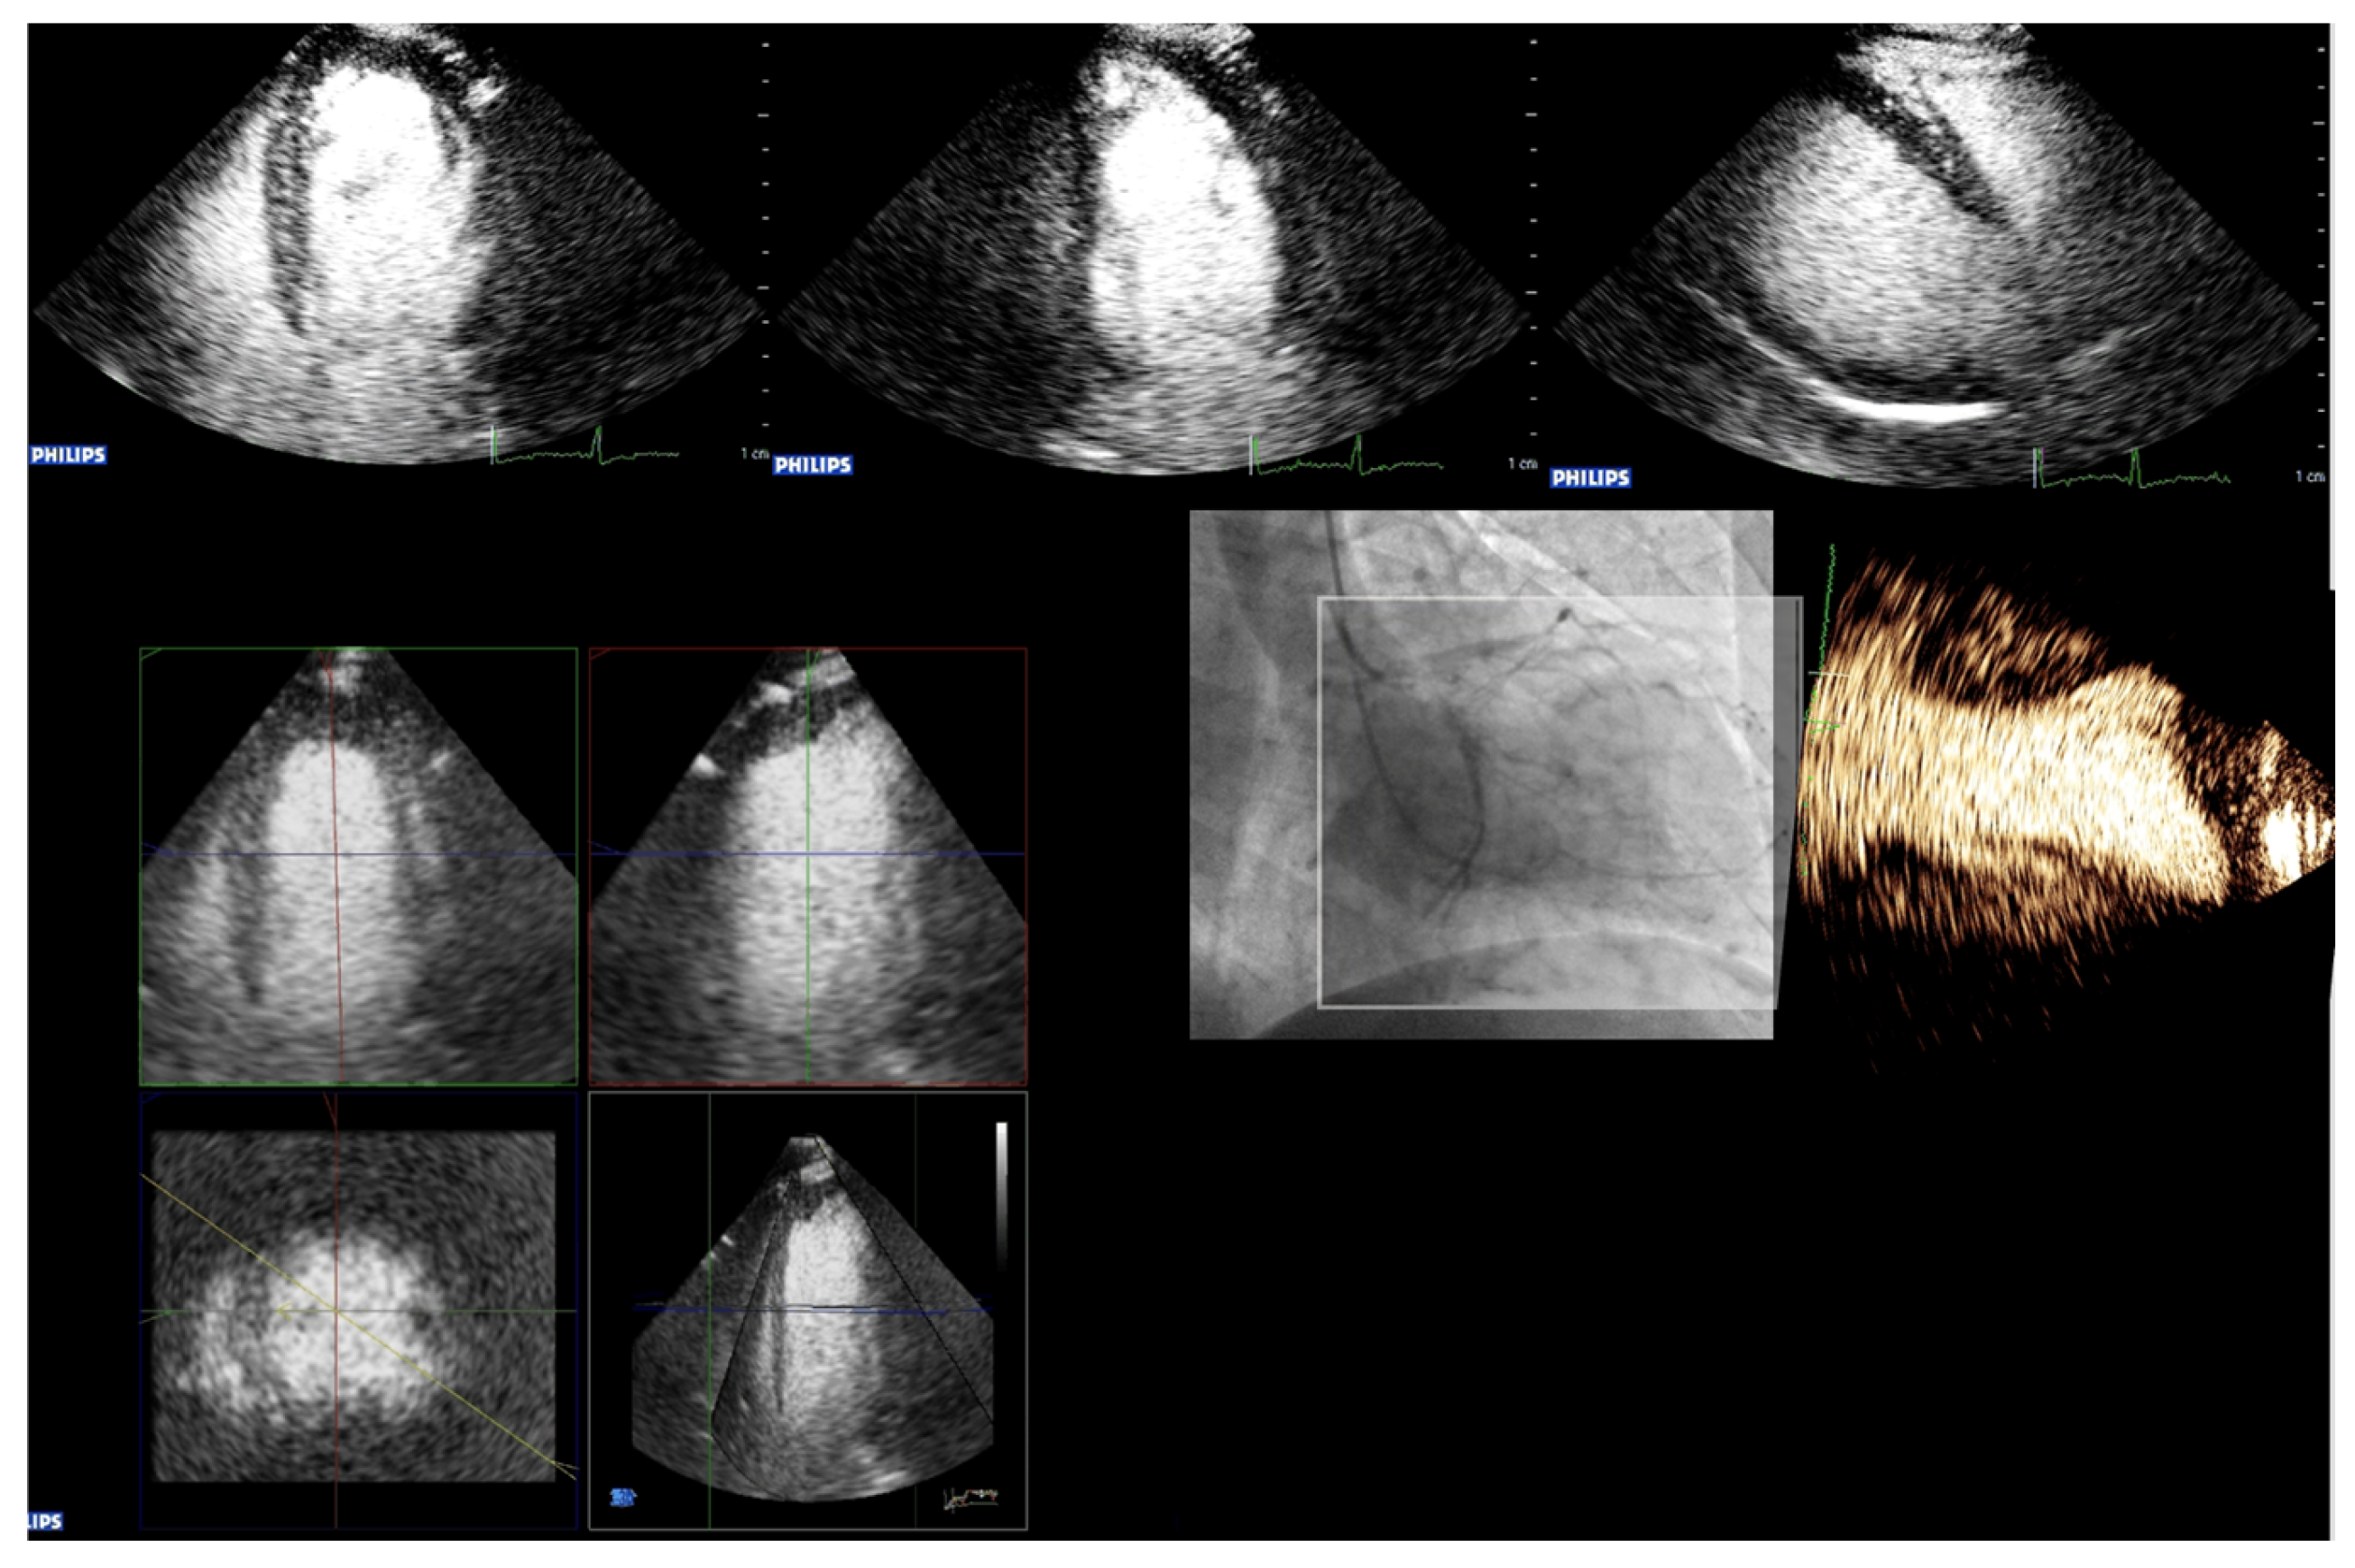

3. Imaging Modalities for UEAs

Perspectives of Imaging Methods and Analysis Tools

4.7. Alternative Imaging Methods